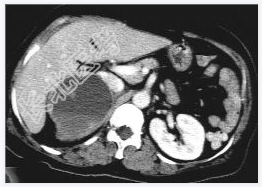

- [材料题] 女性,59岁,胸闷、头晕2天,呈持续性,伴呕吐,以进食后明显。发现“高血压”10年,“糖尿病”2年。体格检查:血压70~210/30~120mmHg。

- 简答题1、该病患诊断是什么?

- 简答题2、鉴别诊断有哪些?

- 简答题3、右肾上腺嗜铬细胞瘤囊变的定义是什么?

- 简答题4、右肾上腺嗜铬细胞瘤囊变的临床意义是什么?

- 简答题5、右肾上腺嗜铬细胞瘤囊变的诊断和治疗上需要注意哪些事项?